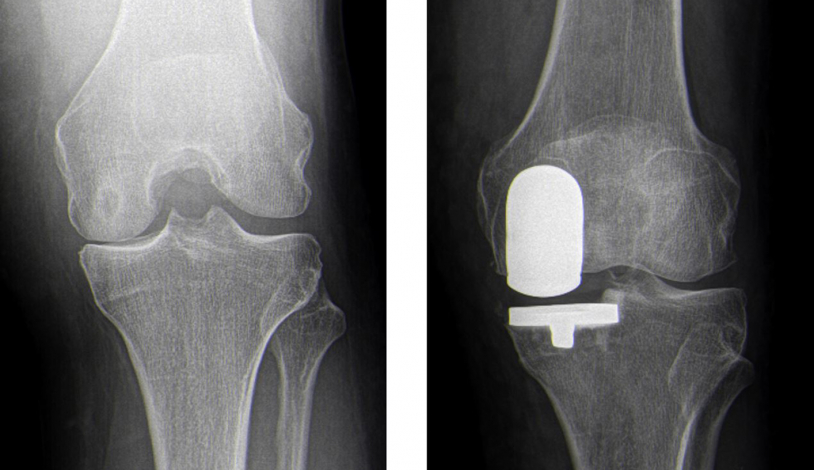

Teilgelenkersatz am Kniegelenk

Betrifft der Verschleiß nur ein isoliertes Kompartiment des Kniegelenkes, kann eine sogenannte „unikondyläre Schlittenprothese“ verwendet werden. Diese hat den Vorteil einer minimalen Knochenresektion sowie den Erhalt einer natürlichen Kniekinematik. Die natürlichen Bänder des Kniegelenks (z.B. vorderes und hinteres Kreuzband) können vollständig erhalten bleiben. Hieraus resultiert eine schnelle Genesung sowie ein natürliches Kniegefühl.